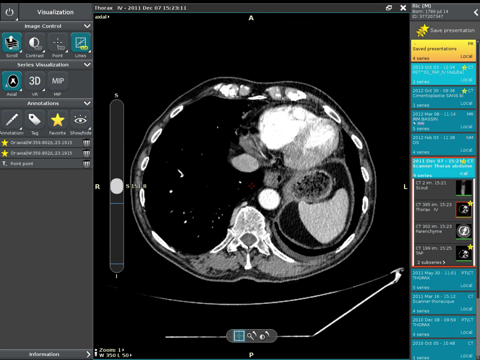

Anywhere Streaming is a DICOM visualization client that connects to Anywhere Server. It provide standard medical image navigation tools surch as : slicing, windowing, MPR, 3D VR, MIP, oblique ... All standard medical image modalities are ...